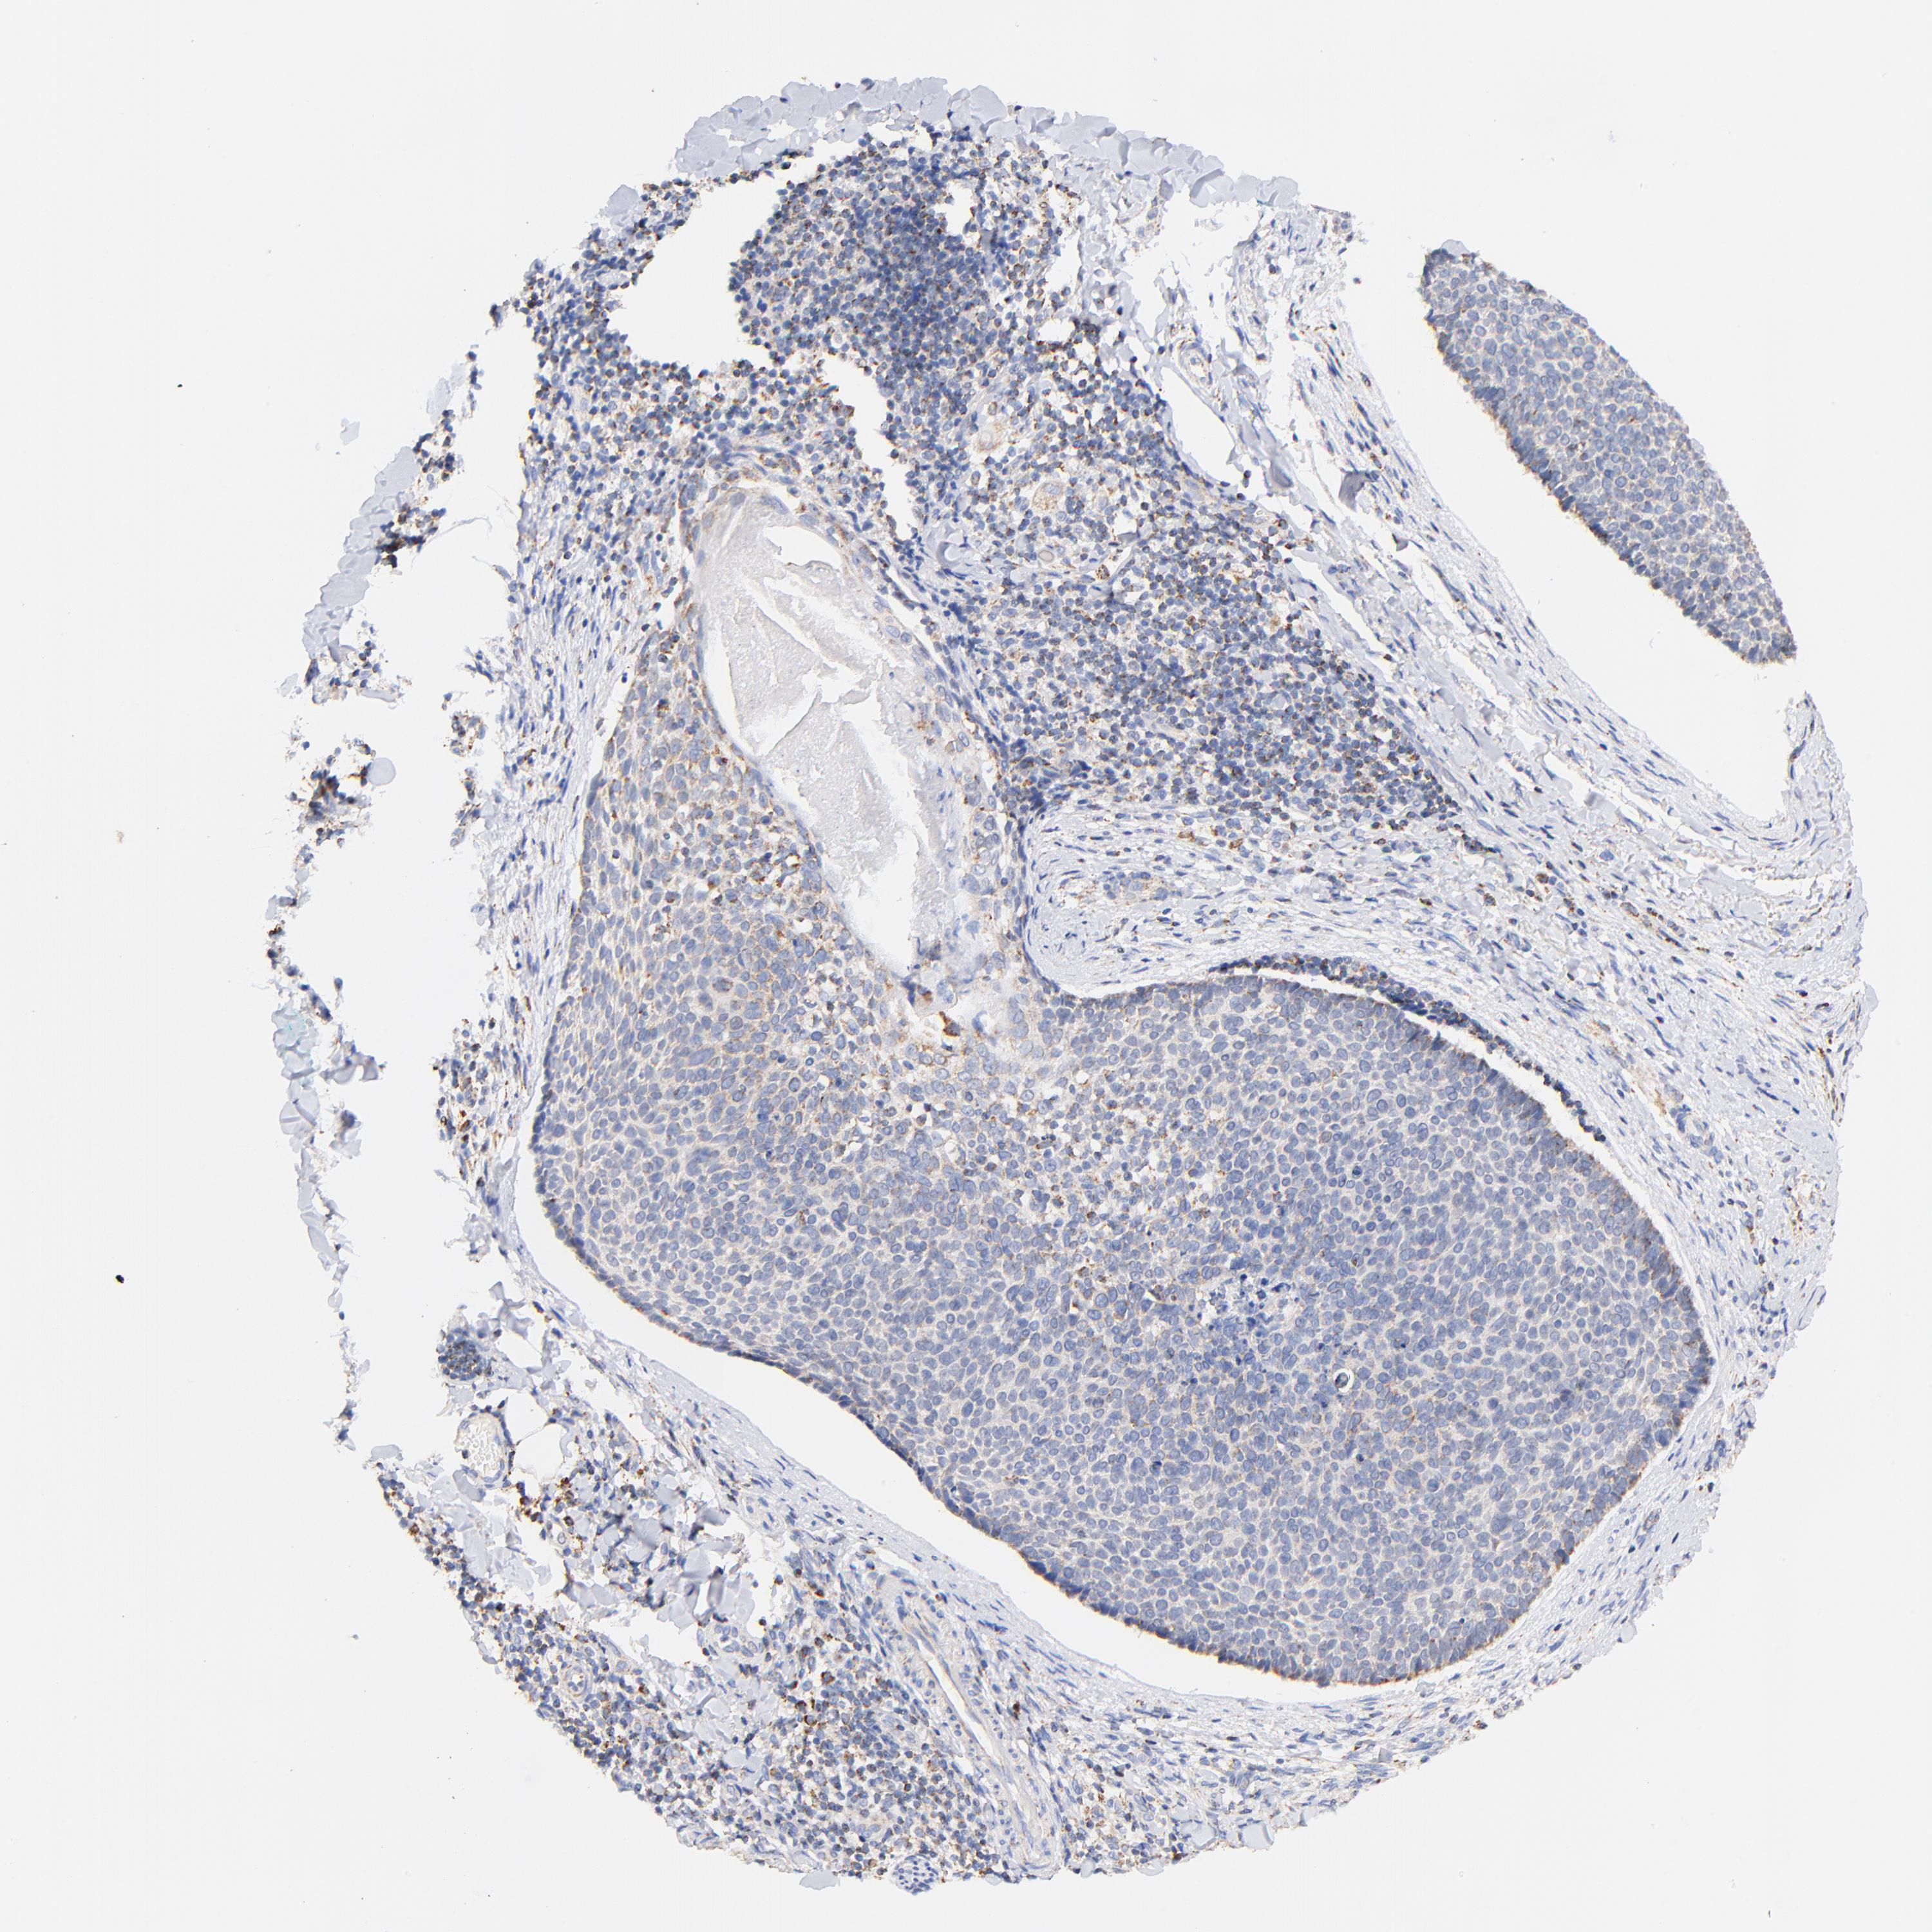

Basal cell and squamous cell cancer

SKIN CANCER - Protein expressioni

A mouse-over function shows sample information and annotation data. Click on an image to view it in a full screen mode. Samples can be filtered based on level of antibody staining by selecting one or several of the following categories: high, medium, low and not detected. The assay and annotation is described here.

Antibody stainingi

Antibody staining in the annotated cell types in the current human tissue is reported as not detected, low, medium, or high, based on conventional immunohistochemistry profiling in selected tissues. This score is based on the combination of the staining intensity and fraction of stained cells.

Each image is clickable and will lead to virtual microscopy that enables deeper exploration of all samples and also displays staining intensity scores, fraction scores and subcellular localization as well as patient and tissue information for each sample.

Antibody HPA002865

Staining

High

Medium

Low

Not detected

Intensity

Strong

Moderate

Weak

Negative

Quantity

>75%

75%-25%

<25%

None

Location

Nuclear

Cytoplasmic/membranous

Cytoplasmic/membranous,nuclear

Squamous cell carcinoma, NOS

Basal cell carcinoma